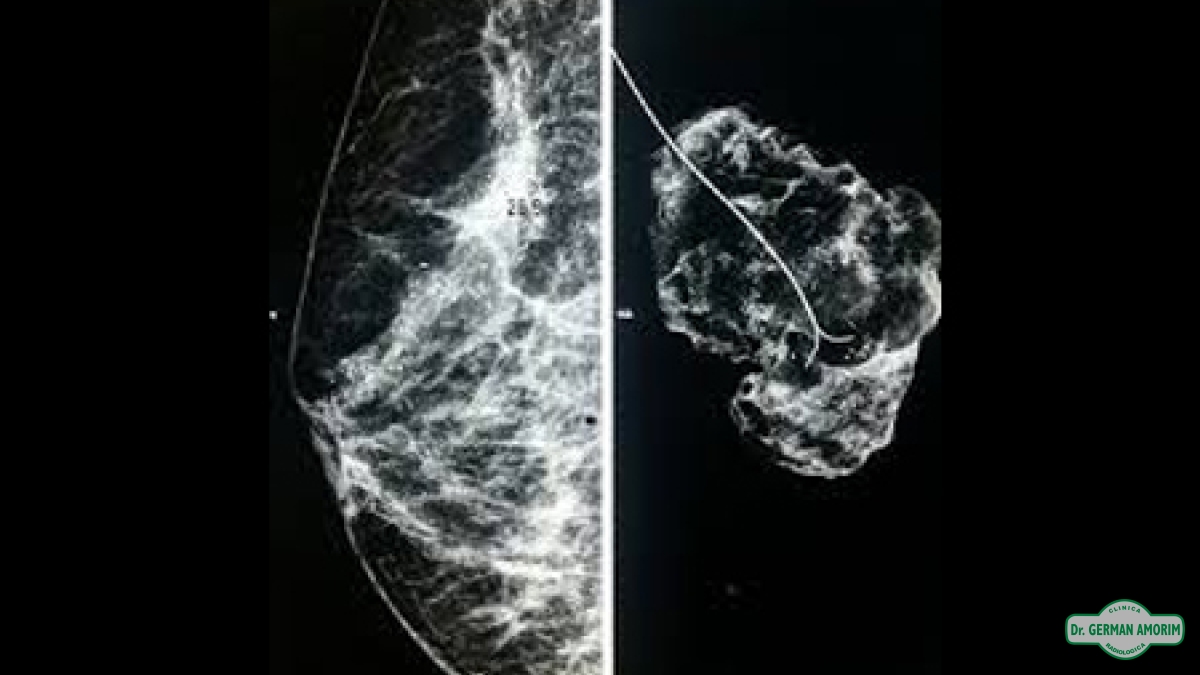

Es la colocación de una guía metálica con un pequeño "anzuelo" en la punta.( para que el mismo no se mueva hasta el momento de la cirugía).

Esta guía, utilizada generalmente en lesiones no palpables o calcificaciones microscópicas, permite la localización intraoperatoria del área a biopsiar o extirpar, lo cual sería imposible de no estar debidamente señalizada por el arpón.Es la colocación de una guía metálica con un pequeño "anzuelo" en la punta.( para que el mismo no se mueva hasta el momento de la cirugía)

El procedimiento no requiere anestesia y es realizado por un médico imagenólogo. En algunos casos puede ser necesario la colocación de más de un arpón o requerir tanto de la ecografía como de la mamografía para asegurar que está situado en el área de interés.